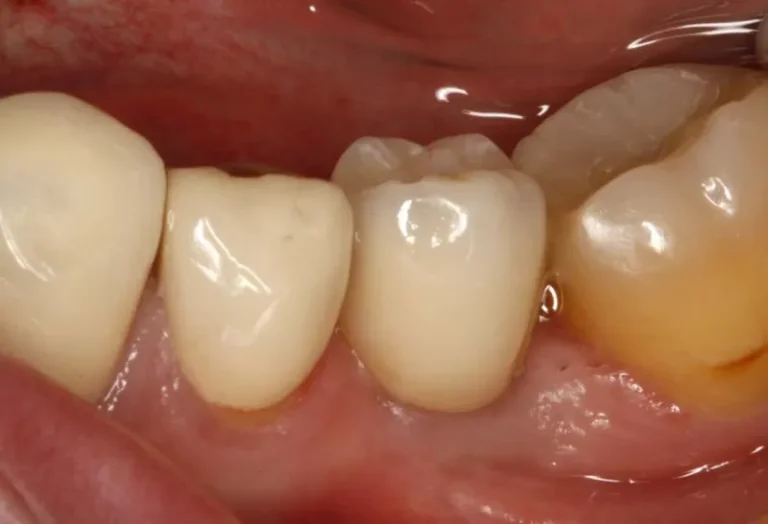

Las diferencias entre implante dental y puente dental son fundamentales para elegir el tratamiento más adecuado. El implante dental consiste en un tornillo de titanio que se inserta en el hueso maxilar, reemplazando la raíz del diente perdido, mientras que el puente dental se apoya en los dientes adyacentes para sostener la prótesis. Aunque ambas…